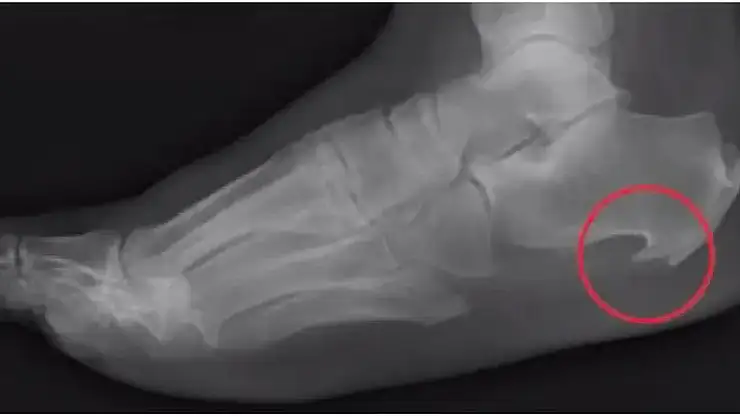

Medical Park Ankara Hastanesi Ortopedi ve Travmatoloji Uzmanı Dr. Öğr. Üyesi Bilgehan Tağrikulu, topuk dikeni rahatsızlığıyla ilgili açıklamalarda bulundu. Topuk dikeninin, topuk kemiğinin alt kısmında kalsiyum birikmesi nedeniyle oluşan kemiksi çıkıntı olarak tanımlandığına dikkati çeken Tağrikuku, “Çoğunlukla ayağın altından geçen ve topuk kemiğini parmaklara bağlayan ‘plantar fasya’ adındaki kalın doku bandının iltihaplanması sonucunda ortaya çıkar. Kronik fasyanın zorlanmasına bağlıtopukta kalsiyum birikimine bağlı olur” diye konuştu.

Topuk dikeninin nasıl anlaşıldığını söyleyen Tağrikulu, topuk ağrısı ile başvuran hastalarda çekilen basit bir düz radyografide değerlendirildiğini ve kolayca tanı konulduğunu vurguladı. Topuk dikeninde tedavi yollarını anlatan Tağrikulu, şunları söyledi: